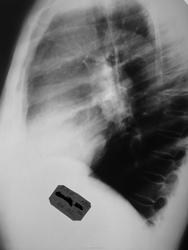

Сегодня сделали контрольный снимок

Приложения:

03102011255_2.jpg

А мне кажется, что не техногенного (см. контрольный снимок). Вполне вероятна ТЭЛА со стертым течением и развитием инфаркт-пневмонии.

Кстати, справа и так его практически нет. Калибр сосудов очень мелкий прямо у самого корня.